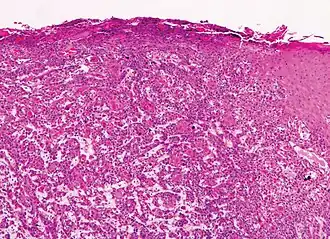

Histological characteristics

Histopathologically, the epidermis in cSCC in situ (Bowen's disease) will show hyperkeratosis and parakeratosis. There will also be marked acanthosis with elongation and thickening of the rete ridges. These changes will overly keratinocytic cells, which are often highly atypical and may have a more unusual appearance than invasive cSCC. The atypia spans the full thickness of the epidermis, with the keratinocytes demonstrating intense mitotic activity, pleomorphism, and greatly enlarged nuclei. They will also show a loss of maturity and polarity, giving the epidermis a disordered or "windblown" appearance.

Two types of multinucleated cells may be seen: the first will present as a multinucleated giant cell, and the second will appear as a dyskeratotic cell engulfed in the cytoplasm of a keratinocyte. Occasionally, cells of the upper epidermis will undergo vacuolization, demonstrating an abundant and strongly eosinophilic cytoplasm. There may be a mild to moderate lymphohistiocytic infiltrate detected in the upper dermis.[12]